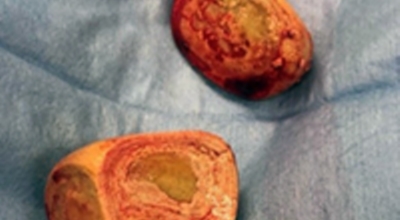

요로결석 치료방법

요로결석의 치료방법은 당연히 결석을 없애주는 방법이 최우선인데요 체외쇼크파 쇄석술 이라고 하는 시술을 통해 결석을 자연 배출될 수 있도록 하는 방법이 있답니다. 쇼크파 장치에서 고에너지 쇼크파를 쬐어 결석을 파괴하면, 결석 조각이 알아서 배출될 수 있도록 하는 시술입니다.

입원이 필요치 않은 시술이며 시술 후 1시간이면 바로 일상 회복이 가능하다고 합니다. 물론 더 심한 경우는 내시경 결석 제거술등의 수술을 통해 제거해야 하는 경우도 있답니다. 그러므로 요로결석 증상이 발생한 초기에 빠르게 대응하여 간단한 시술로 결석을 없애는 것이 최우선입니다.